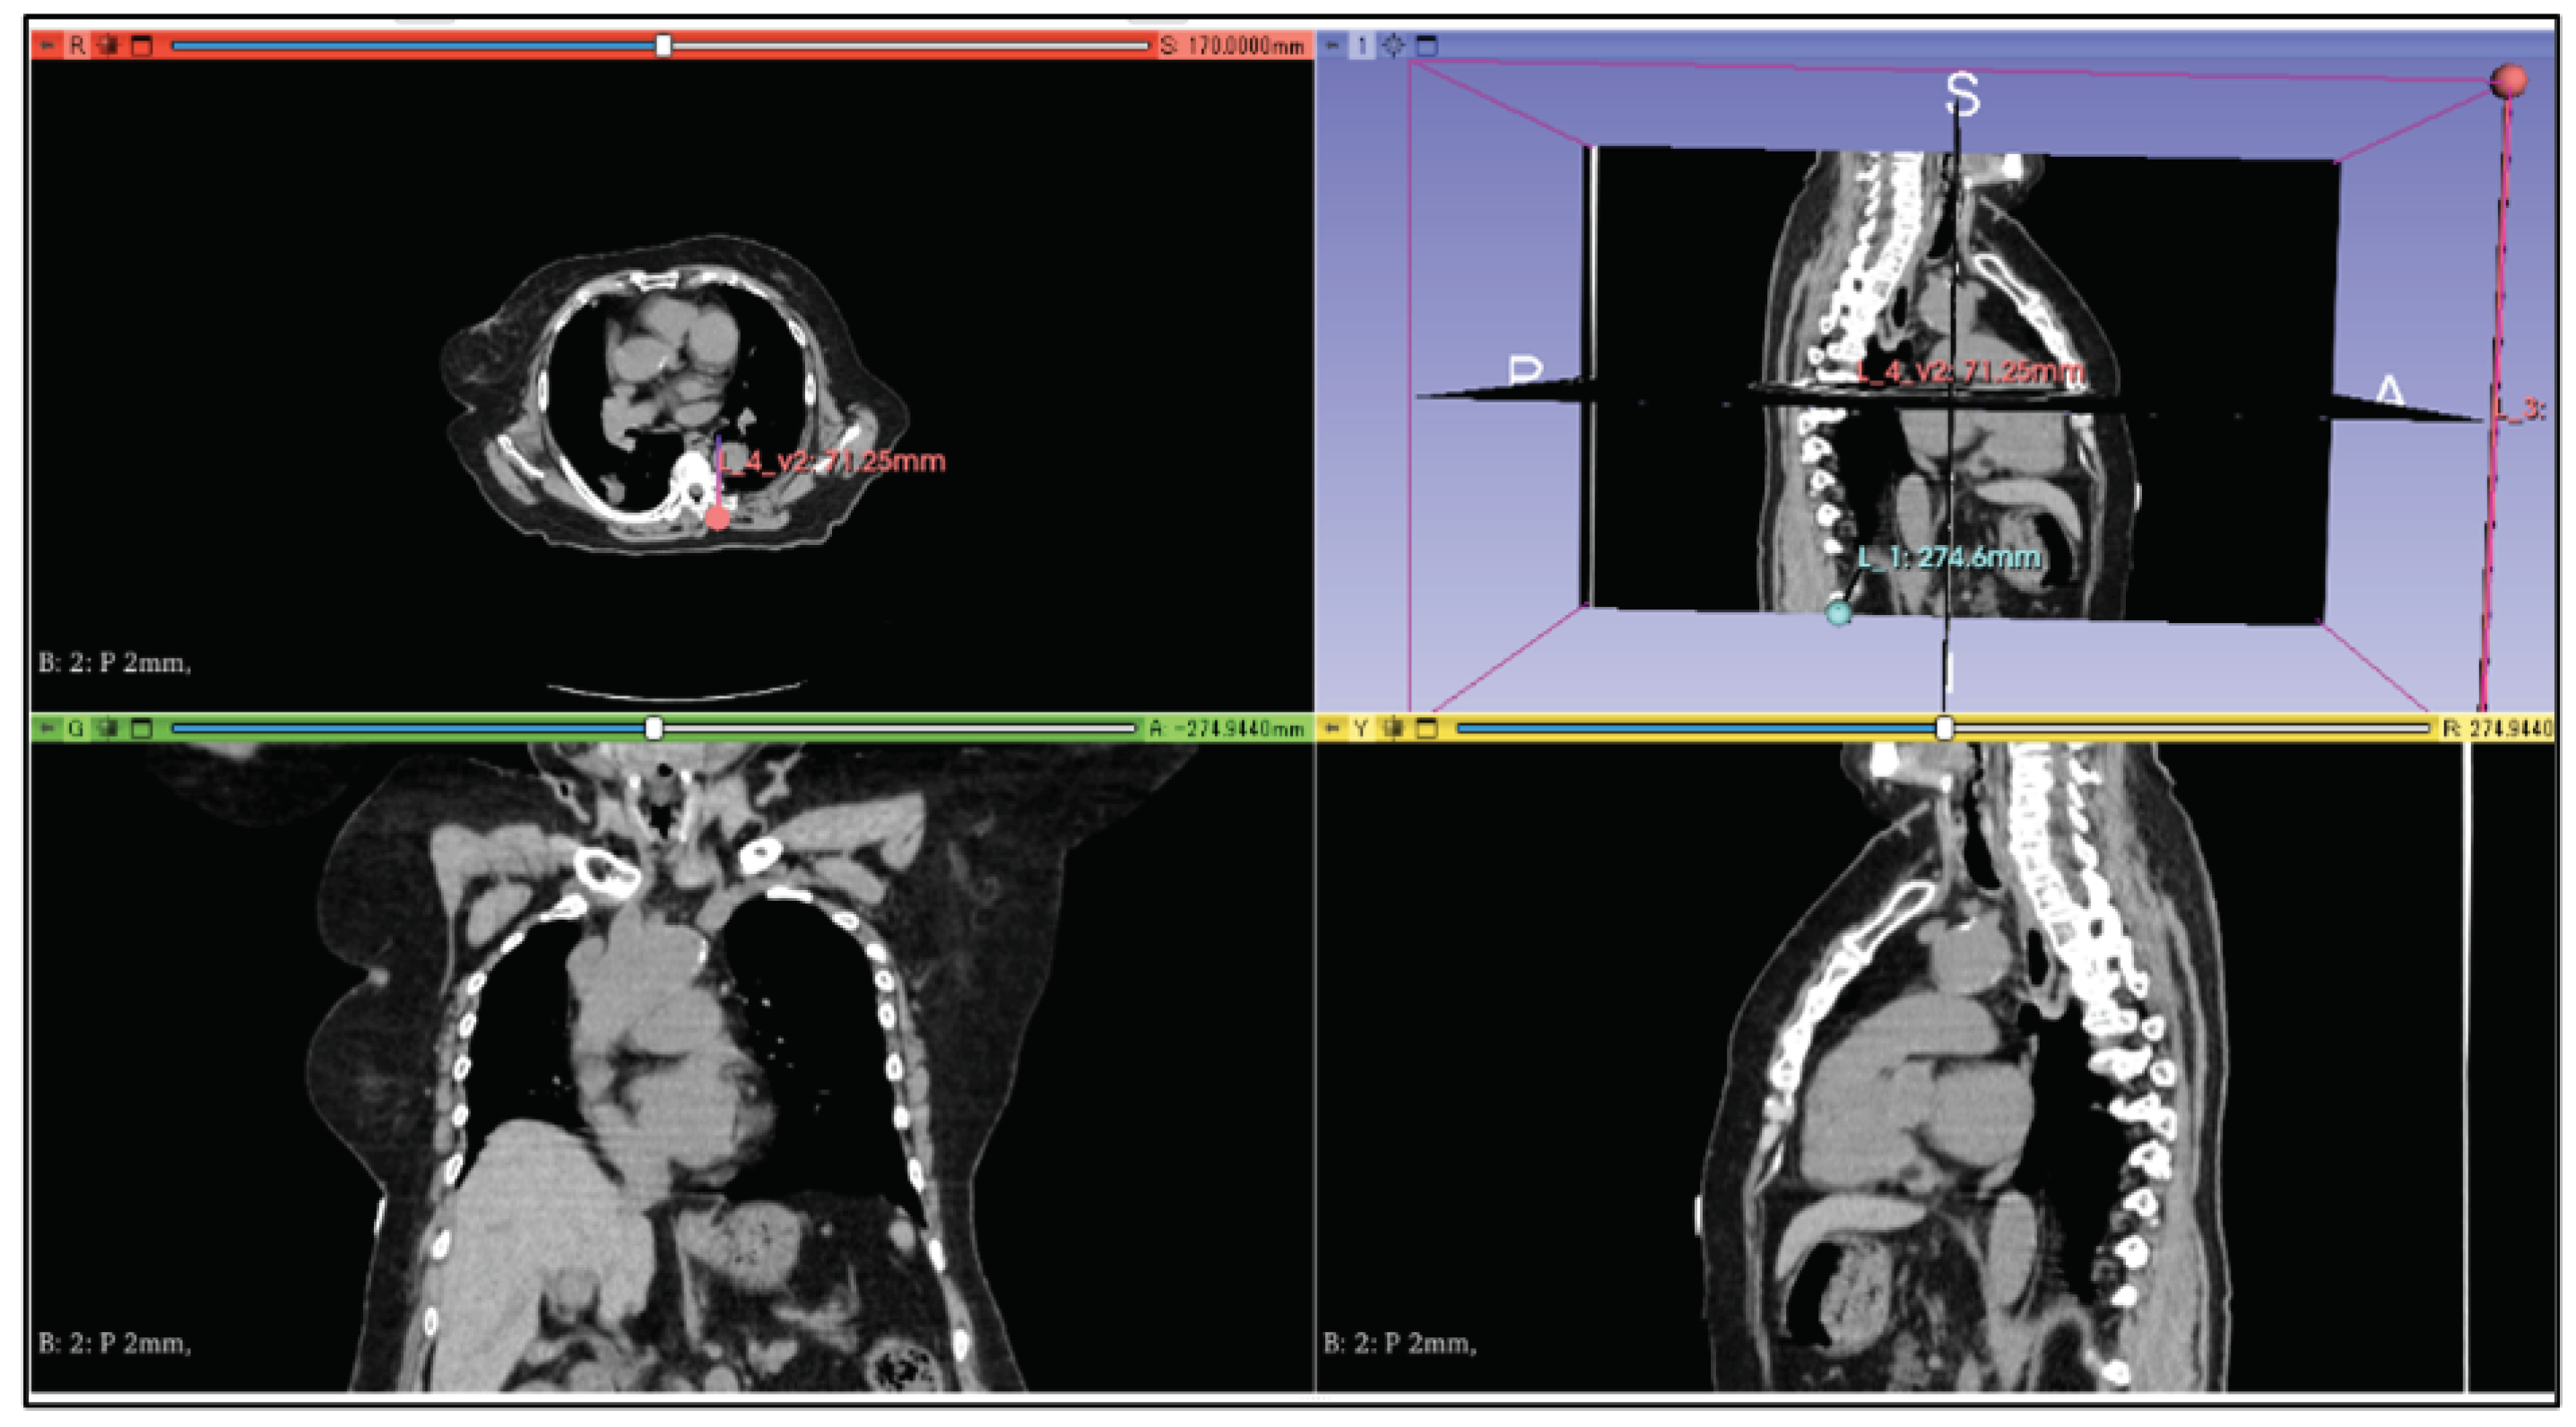

By visualizing the line segment from the target to the coordinates of the puncture start position as a three-dimensional image, a physician can easily determine the puncture route. In this study, we used the 3D Slicer [19] application to visualize the puncture route. An example display of a CT image using the 3D Slicer is shown in Figure 7. 3D Slicer is open source software that can construct three-dimensional images from DICOM data.

The performance of the computer used for the simulation evaluation is shown in Table 2. In this research, we used CT images of one patient with lung masses. In addition, we set two targets at T 1 and T 2 as shown in Figure 9. The coordinates of these two points were T 1 = ( 214 , 345 , 82 ) and T 2 = ( 313 , 315 , 82 ).

6.2. Processing Time to Derive Puncture

Figure 10 shows the puncture routes derived by the proposed method. The red spheres in the figure are the start and end points of the puncture, and the line connecting the two red spheres is the puncture route. In this evaluation, the human body was composed of 170 two-dimensional CT images, and these images were superimposed to create a three-dimensional CT image. The processing time required to derive the puncture route for a three-dimensional CT image using all 170 two-dimensional CT images was approximately 59.4 s.

Figure 7. Example of a CT image using 3D Slicer.

Jimaging 10 00251 g007

Figure 9. Coordinates of targets T 1 and T 2 .

Jimaging 10 00251 g009